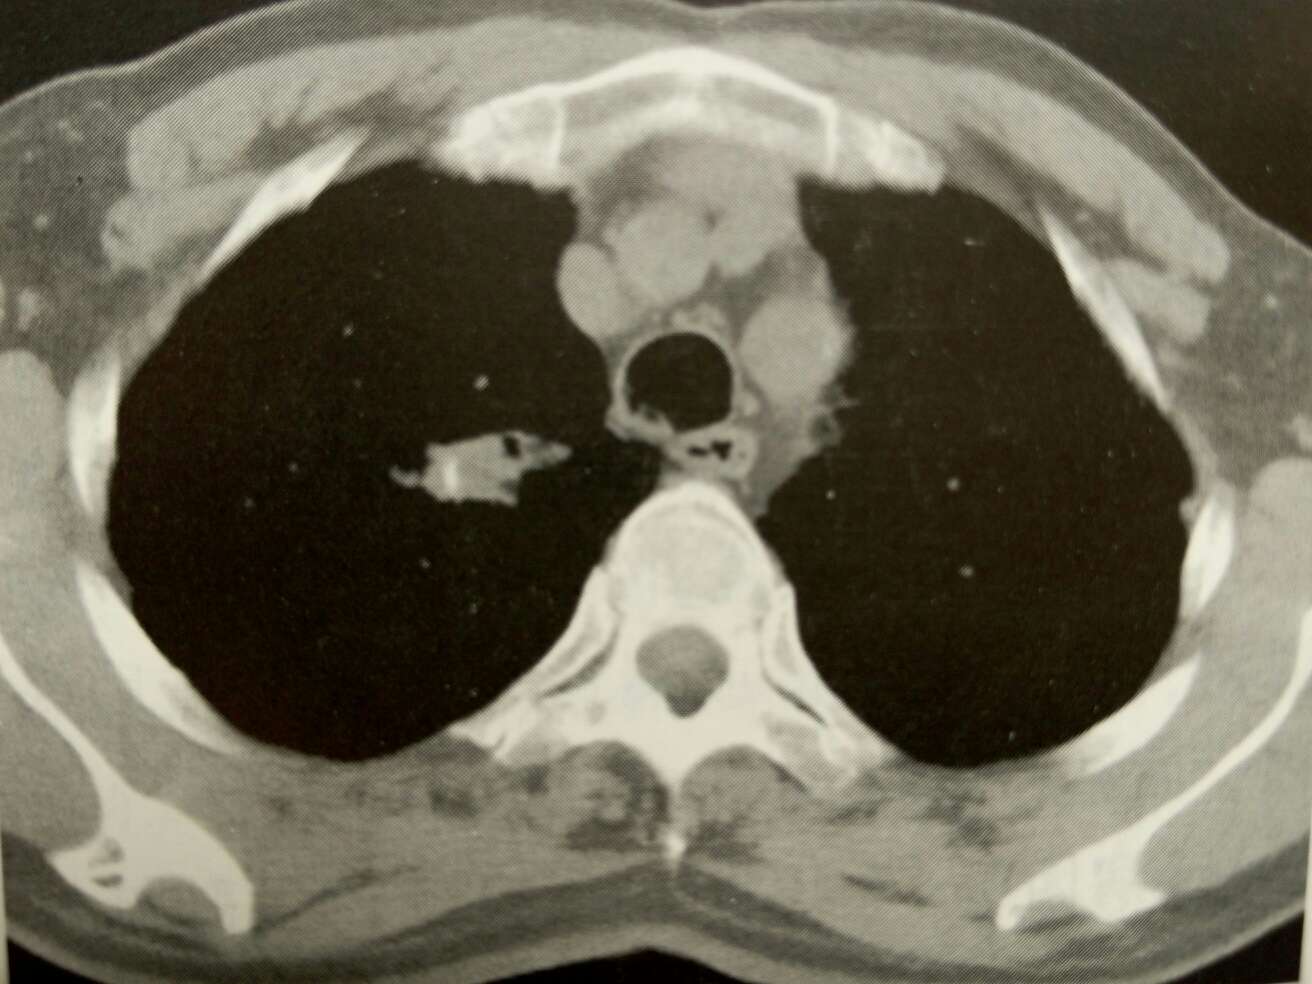

矽肺 ( silicosis )